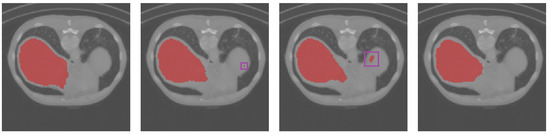

3.3. Results Obtained on the Spleen and Liver CT Datasets

| Dice | TPR | TNR | HD95 | |

|---|---|---|---|---|

| U-Net | 55.88% | 42.11% | 99.15% | 8.77 |

| UNet++ | 58.78% | 46.28% | 98.90% | 8.00 |

| Att-UNet | 60.16% | 50.82% | 98.21% | 6.40 |

| Focus-UNet | 46.10% | 38.36% | 97.24% | 8.06 |

| SAB-Net | 61.13% | 50.27% | 98.60% | 7.07 |

| U-Net | 60.12% | 56.72% | 99.93% | 4.99 |

| UNet++ | 68.93% | 59.93% | 99.97% | 6.32 |

| Att-UNet | 72.37% | 61.77% | 99.98% | 5.74 |

| Focus-UNet | 68.13% | 55.16% | 99.97% | 7.01 |

| SAB-Net | 74.31% | 63.05% | 99.98% | 4.24 |